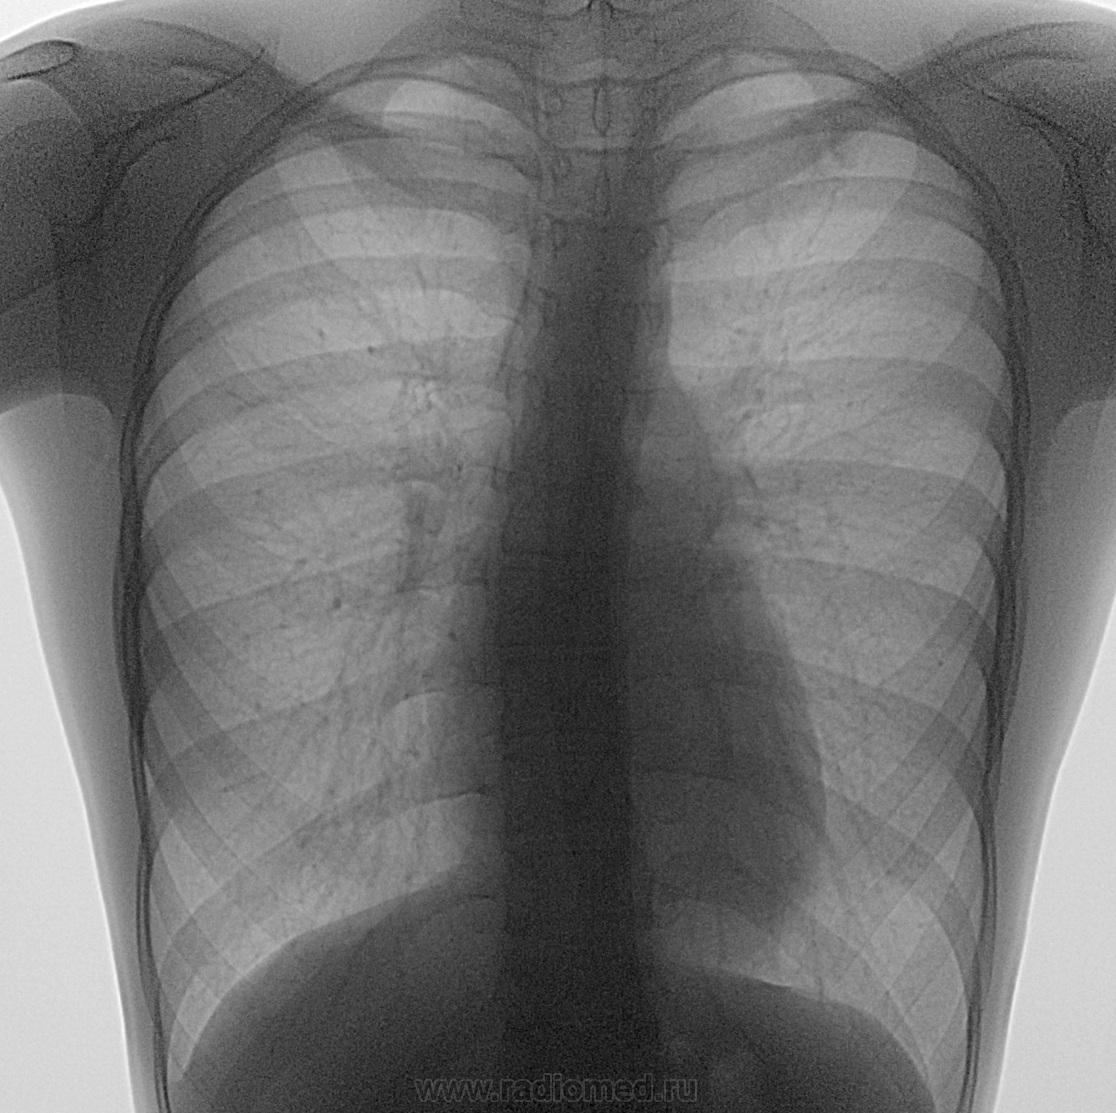

Перелом I ребра слева?

Ежегодная ФЛЮ март 2013г.

Похоже, но интересно, какой механизм травмы.

Думаю не перелом. Подозрение на очаговоподобные тени и сгущение л. рисунка.

Очень похоже на недоразвитое ребро. Дистальная часть - хрящ.

Рассмотрел бы вариант срессового перелома http://www.jssm.org/vol8/n2/22/v8n2-22pdf.pdf

Еще мне не нравится бочкообразная форма грудной клетки (косвенный признак бронхиальной обструкции), рек. ФВД.

Присмотритесь внимательнее, и в 2013 г. было линейное просветление 1-го ребра слева именно на этом месте, на последнем снимке расхождение отломков (т.е. неконсолидированный перелом).

Вы имеете в виду формирование ложного сустава?

Да, именно так!

Согласен, недосмотрел. Тогда вариант стрессового перелома (лоозёровская зона). Скорее всего человек левша.

Согласна с Андреем Юрьевичем, нечасто, но встречается, причем интересно, что обычно не беспокоит пациента вне зависимости от степени срастания